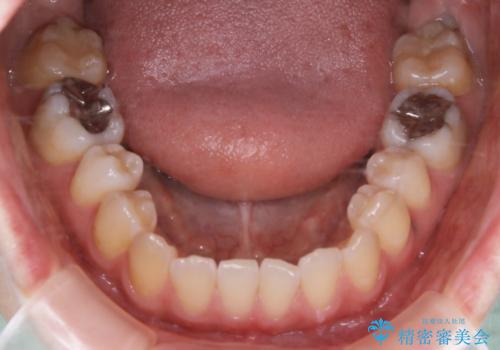

- 受け口で、前歯の嚙み合わせが気になるとの事でご相談にいらした方です。先天的に右上犬歯がなく、左上犬歯も小さい状態でした。矯正治療にて周囲の歯を動かして歯のスペースを確保した上で、被せものにて歯を作っていきました。

歯科技工士さんの熟練した技術により、周囲の歯としっかりなじむ天然歯のような被せ物をお作りすることが出来ました。

矯正治療と補綴治療をうまく組み合わせることで、美しい口元に仕上げることが出来ました。矯正治療、補綴治療をまとめて行える総合歯科治療を体現した治療といえます。